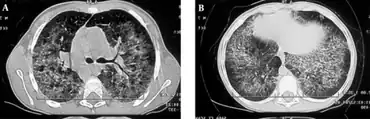

Diagnostic method | MRI, Chest radiography[1] |

The diagnosis of hyper IgM syndrome can be done via the following methods and tests:[1]

- MRI

- Chest radiography